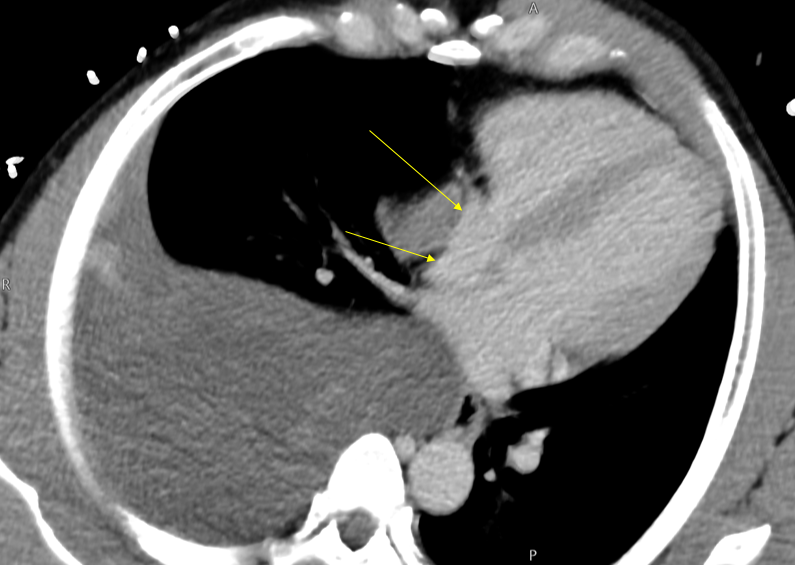

Attention to #spectral images! Gopal Punjabi ⚠️ The endobronchial content is enhancing --> solid! 1️⃣Virtual non-contrast (VNC)= 39HU 2️⃣Conventional= 71UH (>20UH compared to VNC) 3️⃣ Iodine density =1.26 mg/ml